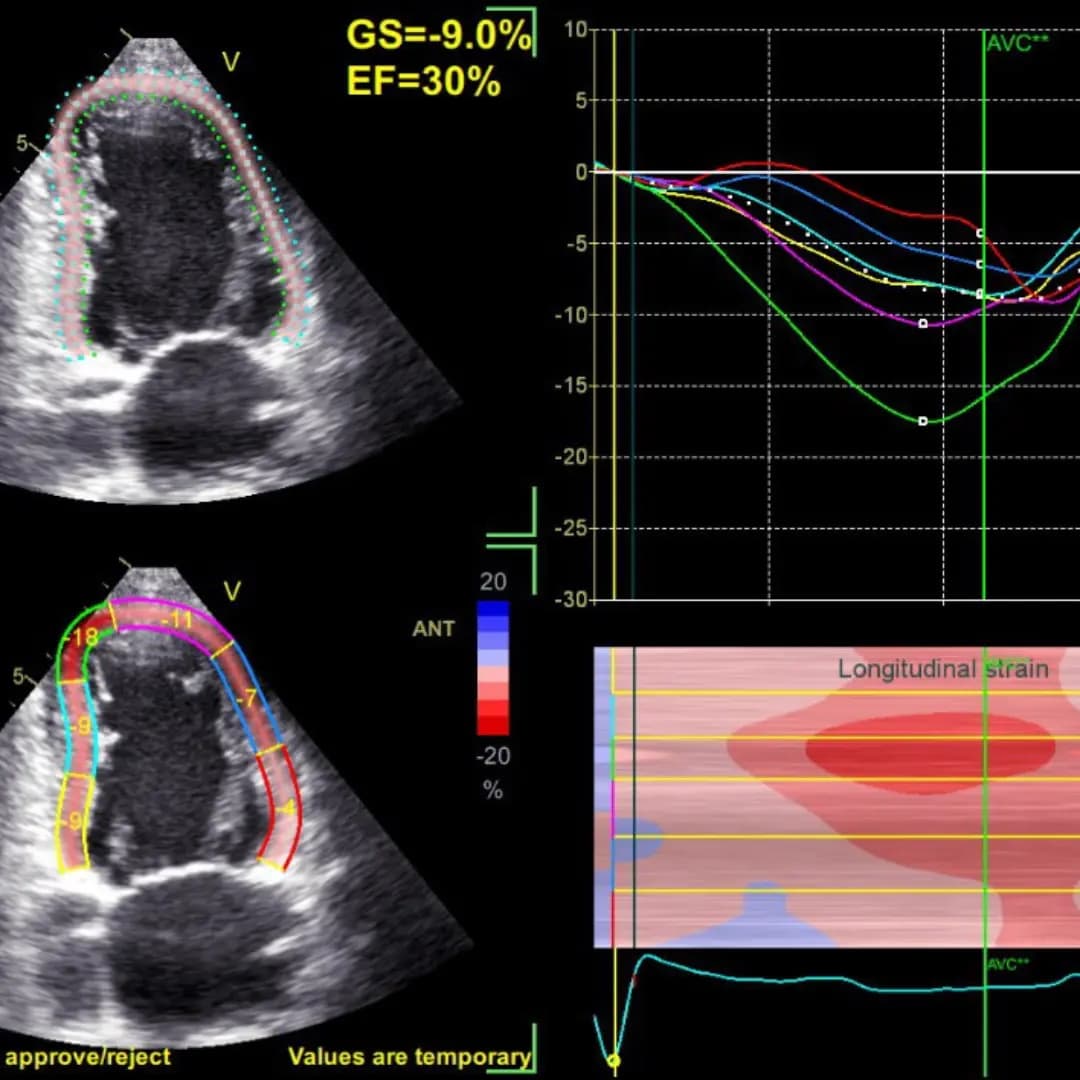

Стрейн ЕхоКГ (спрекл-трекінг) – це сучасна діагностична методика, яка доповнює та розширює можливості звичайного УЗД серця (ЕхоКГ) та дозволяє краще оцінити скоротливість міокарда, тобто ефективність роботи серця як насосу.

Результат отримується разом із результатами стандартної ЕхоКГ. Це додаткові діаграми та графіки.